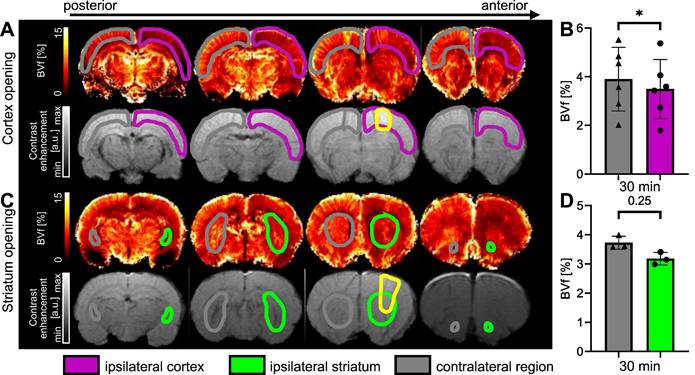

Assessment of BVf 30 minutes after BBB disruption

The measurements of BVf in the cortex targeted by FUS (ipsilateral) and in the contralateral cortex were calculated from MGE images acquired before and after injection of USPIO nanoparticles [31]. The results, expressed as a percentage of blood occupying the voxel, are shown in Figure 8. Figure 8A illustrates the reduction in BVf values in the targeted cortex extending beyond the open area (highlighted in yellow on the T1-w after Gd-DOTA injection). It should be noted that Gd-DOTA was injected after USPIO, and this does not prevent the observation of contrast enhancement of Gd-DOTA on T1-w images [40]. A significant reduction in BVf was measured (p = 0.0313). The average reduction in BVf was 13% (3.9 ± 1.3% in the contralateral cortex and 3.4 ± 1.2% in the ipsilateral cortex) (Figure 8B). To evaluate the response in the striatum, a further set of three animals was employed (Figure 8C). No significant difference was observed when the BBB was opened in the striatum, with an average BVf of 3.18 ± 0.2% in the ipsilateral striatum and 3.73 ± 0.2 % in the contralateral striatum (Figure 8D). Consequently, the BVf was found to be reduced by 15% in the ipsilateral region, thereby confirming vasoconstriction across the entire area.

Figure 8

Examples of BVf maps 30 min after BBB opening in the cortex (A) and in the striatum (C), together with associated T1-w images following Gd-DOTA injection. The BBB-opened area is delineated in yellow. BVf was quantified 30 min after FUS in the cortex (B) and in the striatum (D). The data were analysed using a two-tailed non-parametric test (Wilcoxon) (*p < 0.05). The results are expressed as mean ± S.D.